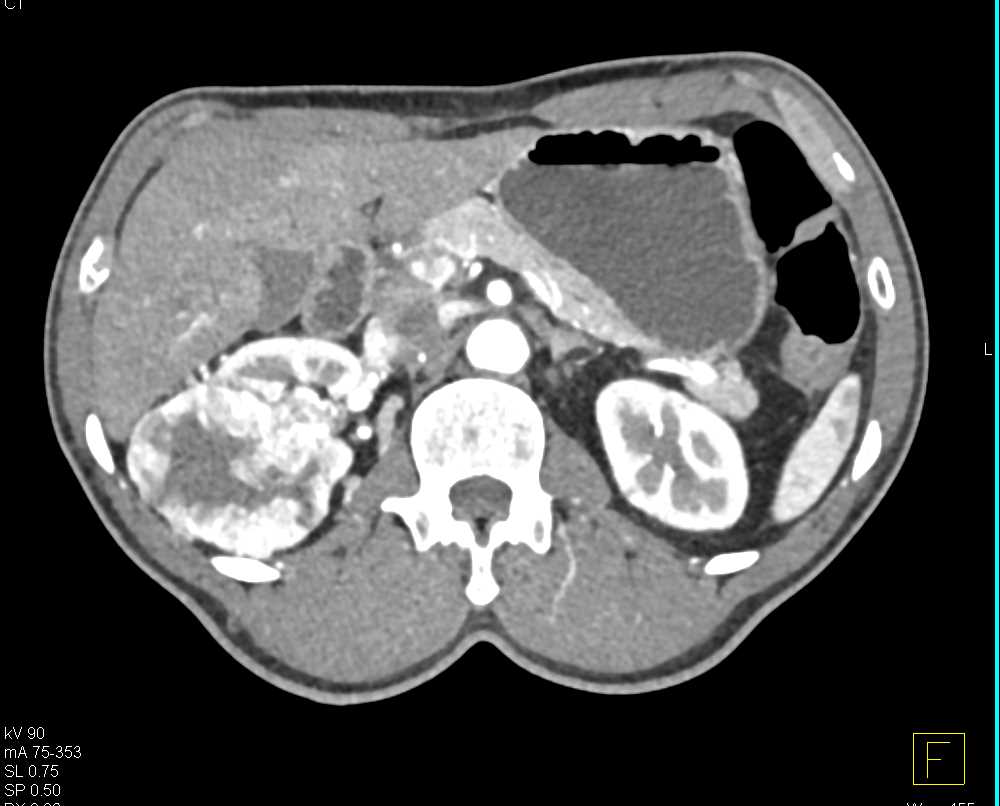

Clear Cell Renal Cell Carcinoma (CCRCC) Right Kidney